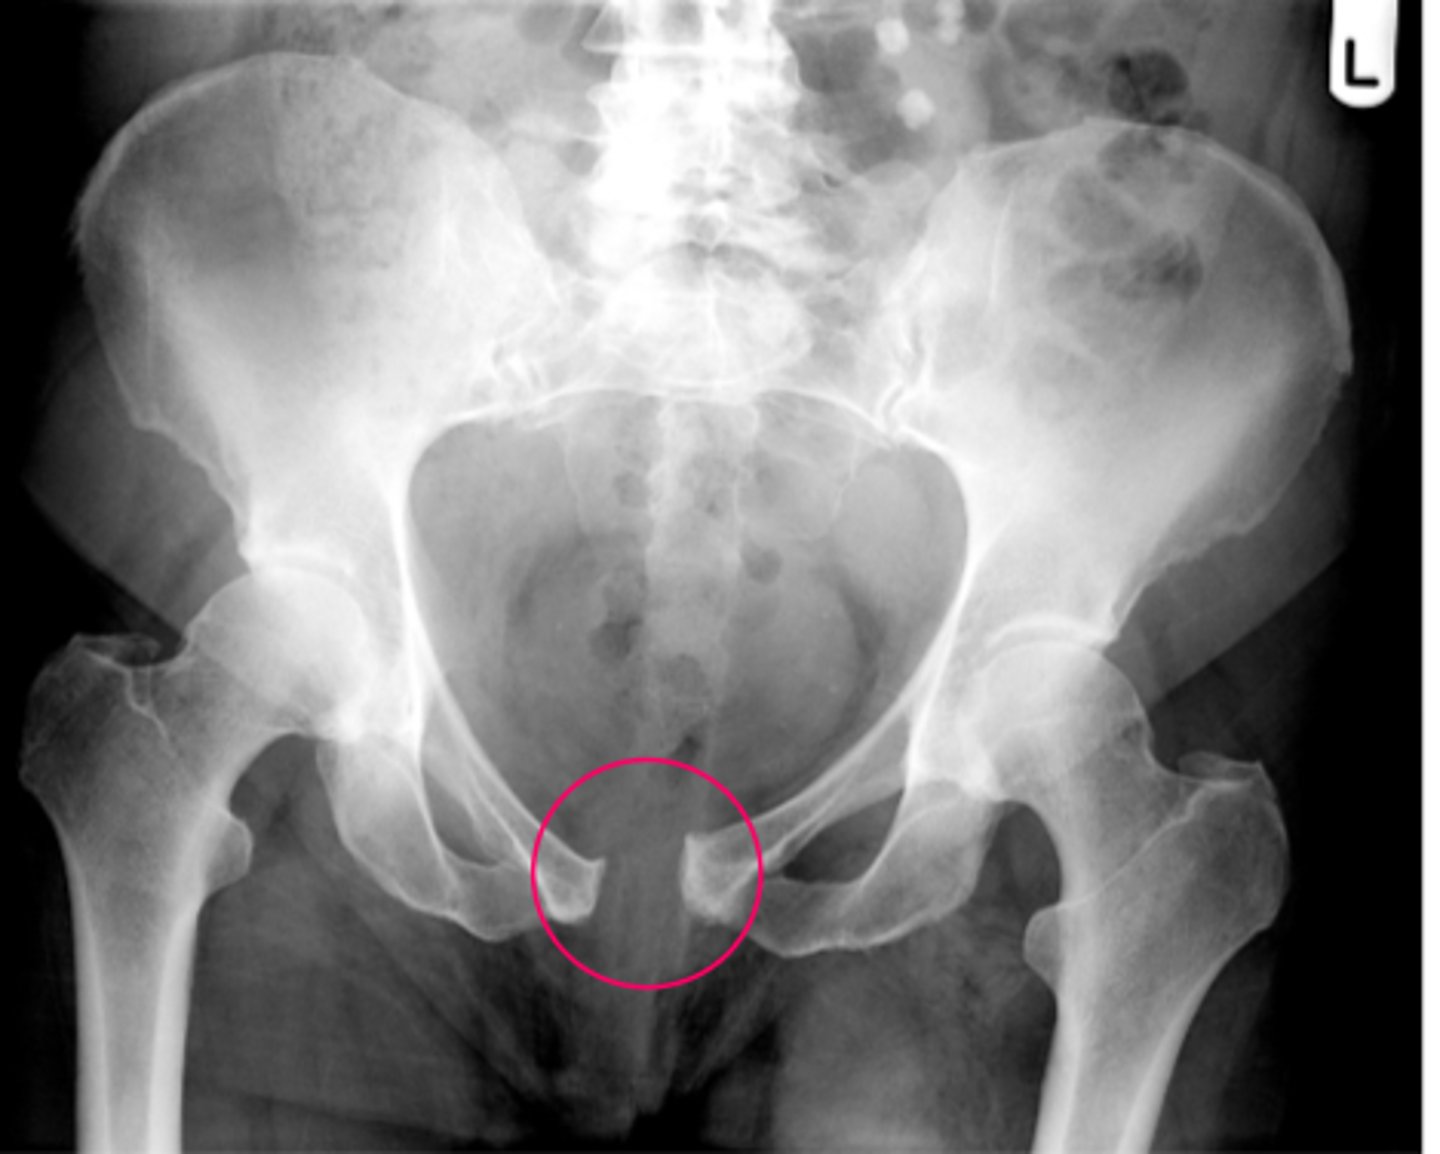

slipped capital femoral epiphysis

gradual or acute failure of the epiphyseal plate of the head of the femur due to shear forces parallel to the growth plate, causing the head to slide posterior/inferior

*may be related to trauma, inflammation, obesity, or hormonal factors

**more likely in males, onset approx 13 yrs of age (10-17)

FUNCTIONAL DEFICITS--> pain, gait changes (antalgic pattern)

COMPENSATORY MOVEMENTS--> may result in growth deficits, complications include avascular necrosis

posterior/inferior

In which direction(s) does the femoral head slide in a patient with slipped capital femoral epiphysis?